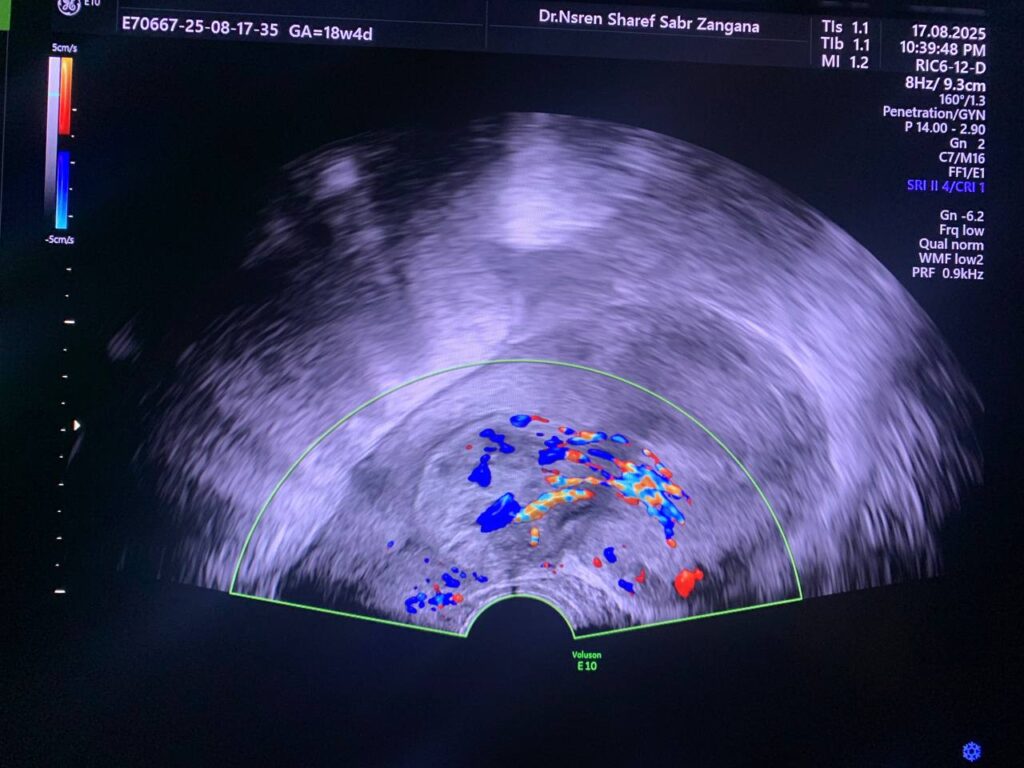

presence of vascular heterogeneous mass 28x45mm in the lower uterine cavity and internal os level , arise from the right sided anterior wall , pedunculated submucosal fibroid can not be excldued .